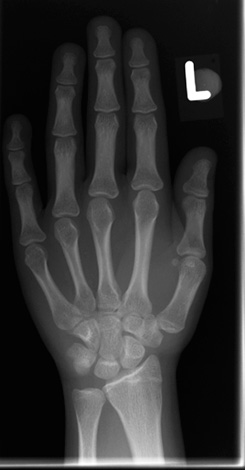

Dos métodos diagnósticos adicionais, os exames radiológicos são obrigatórios:

- Radiografia da mão da criança - realizada na adolescência, a fim de entender em que estágio do crescimento ósseo a criança está atualmente (isso é importante para a escolha do melhor plano de tratamento);